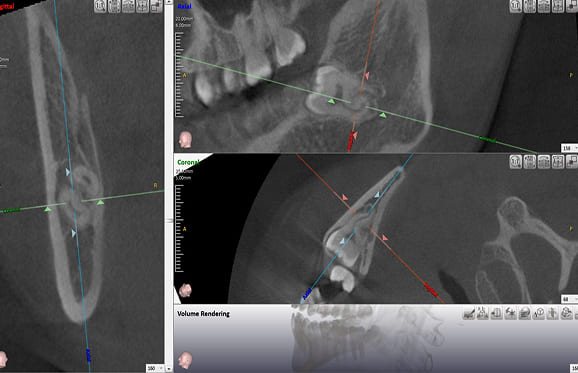

● 下の顎の親知らず抜歯 2回法

藤沢デンタルオフィスの親知らず抜歯

01 神経に近い位置に親知らずの根が存在

02 親知らずの頭の部分だけ抜歯

03 親知らずの根の部分が神経から離れる

下の顎の親知らずの抜歯では、神経の損傷リスクを考えて2回に分けて抜歯する場合があります。 また、麻酔が効きにくい場合にも、同様に2回に分けて抜歯します。